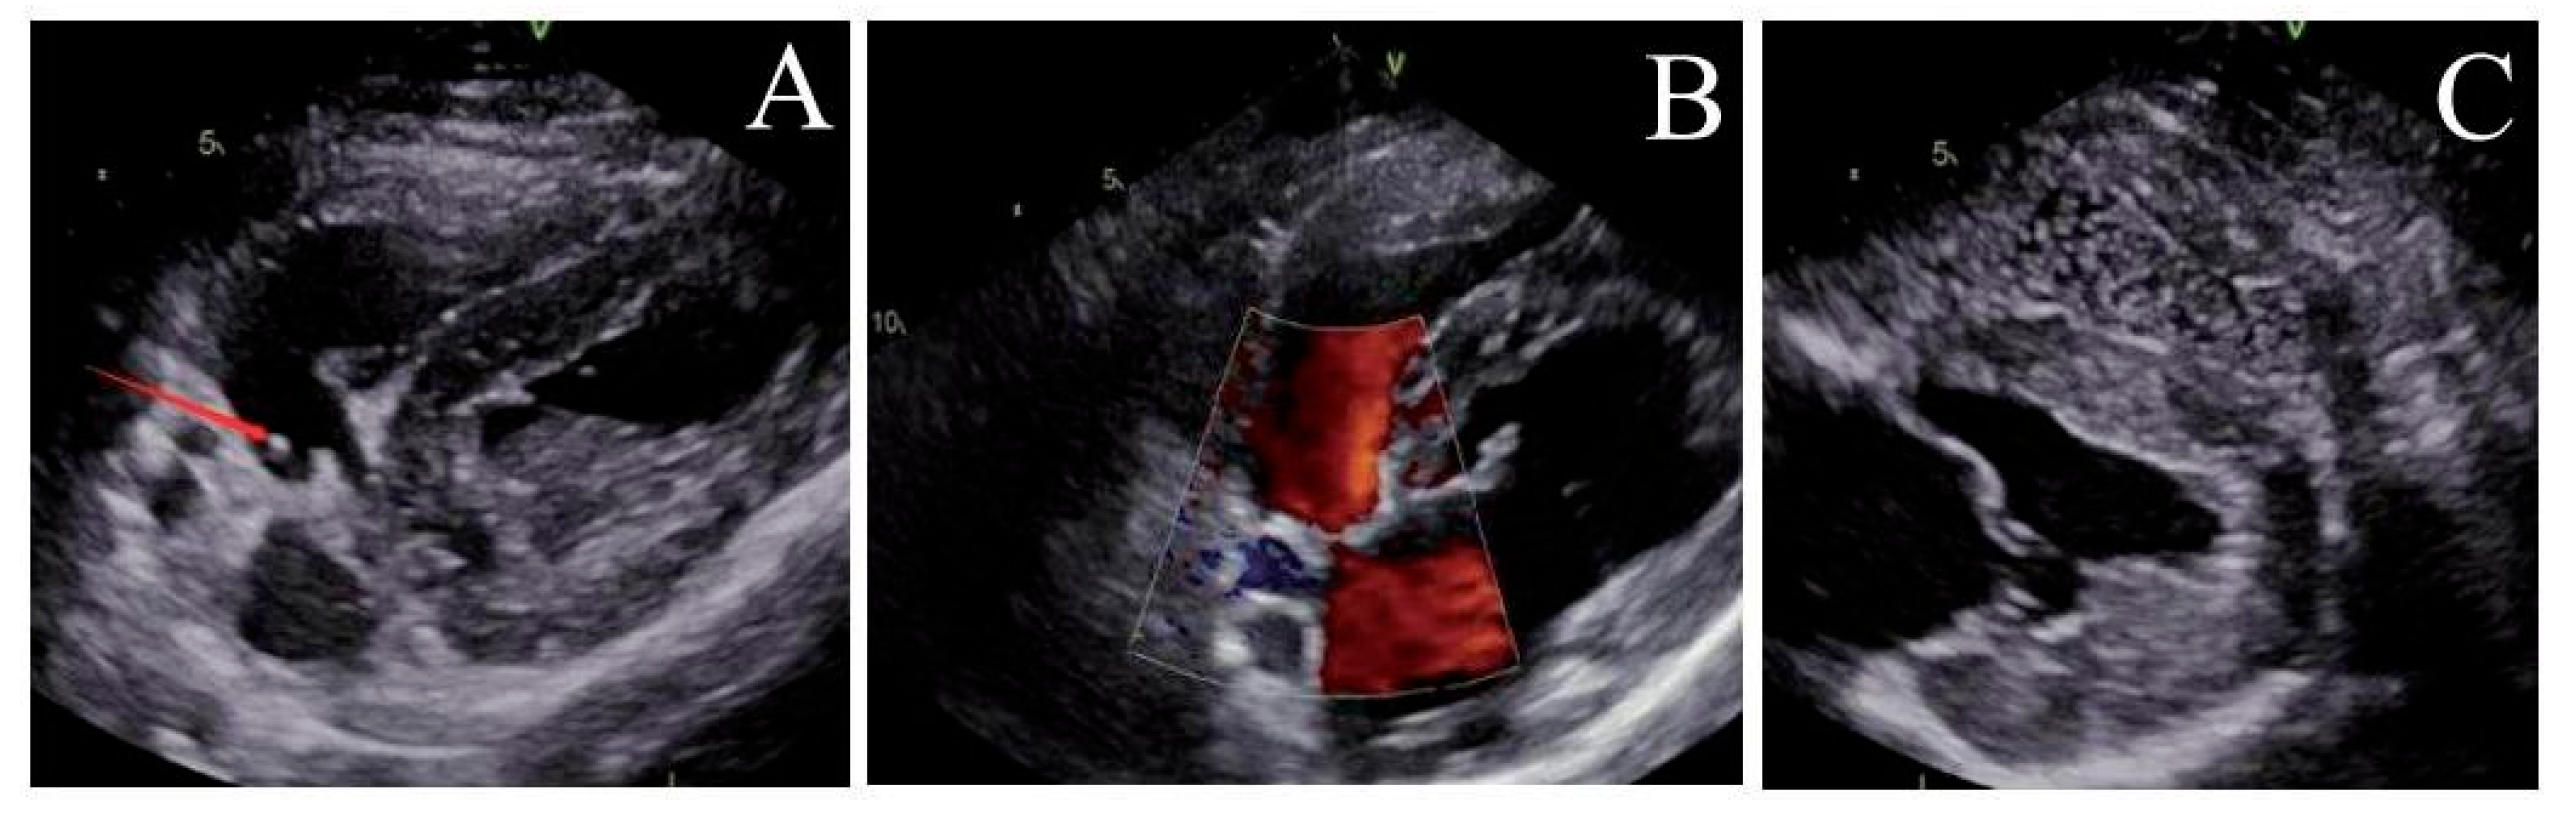

Post-implantation, the locking mechanism remained stable without suture breakage, thrombus formation, or neoplastic changes. The locking device was clearly visualized on ultrasound. Both the atrial septal defect diameter and residual shunt flow velocity decreased significantly over time, with near-complete defect closure observed by 6 months (postoperative ultrasound at immediate, 1, 3 and 6 months respectively, Fig. 3, Fig. 4, Fig. 5 and Fig. 6). Left ventricular hemodynamics and function remained unaffected.

Figure 3: Immediate postoperative ultrasound observation. (A) The locking node is intact, (B) the size of the atrial septal defect is significantly reduced, and (C) there are a few bubbles in the left atrium.

Figure 4: Ultrasound observation one month after operation. (A) The locking node is intact, (B) the size of the atrial septal defect further decreases, and (C) there are trace bubbles in the left atrium.

Figure 5: Ultrasound observation three months after operation. (A) The locking node is intact, (B) the size of the atrial septal defect further decreases, and (C) there is no bubbles in the left atrium.

Figure 6: Ultrasound observation six months after operation. (A) The locking node is intact, (B) the size of the atrial septal defect further decreases, and (C) there is no bubbles in the left atrium.